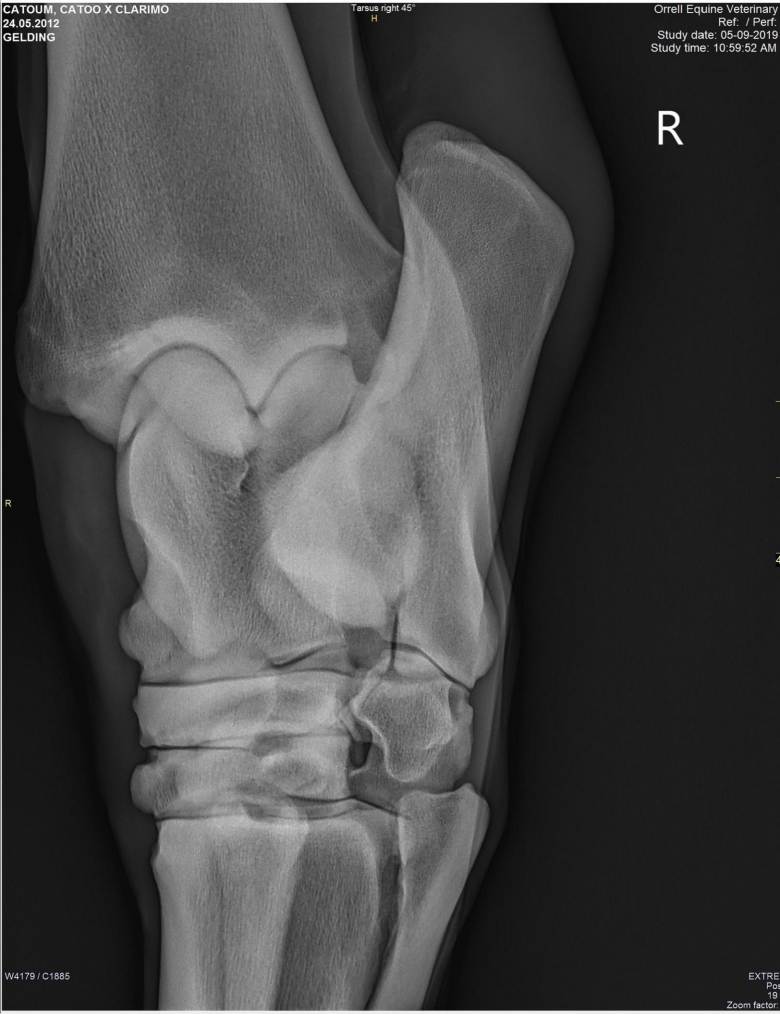

Snart dök det även upp röntgenplåtar, utan att Marina ens hade frågat efter dem. Röntgenbilderna skickade Marina vidare till två olika veterinärer för bedömning. Bägge såg lösa benbitar i ena hasen och Cecilia Grahn på Kungsbacka Hästklinik hade en mejlkonversation med den engelske veterinären ”Steve Orrell” som hade tagit bilderna. Att bilderna var falska och att det inte var den riktige Steve Orrell var det ingen som visste då. Han skrev att han hade sett hästen sedan den var tre år och argumenterade först emot de tre lösa benbitar som Cecilia Grahn hade hittat.

Lucas Bailey skickar bilder på röntgenplåtar. Marina Johansson låter två olika veterinärer bedöma bilderna. Bägge såg lösa benbitar i ena hasen och Cecilia Grahn på Kungsbacka Hästklinik hade en mejlkonversation med den engelske veterinären ”Steve Orrell” som hade tagit bilderna. ”Veterinären” skriver att han har sett hästen sedan den var tre år och argumenterar för att benbitarna saknar betydelse.